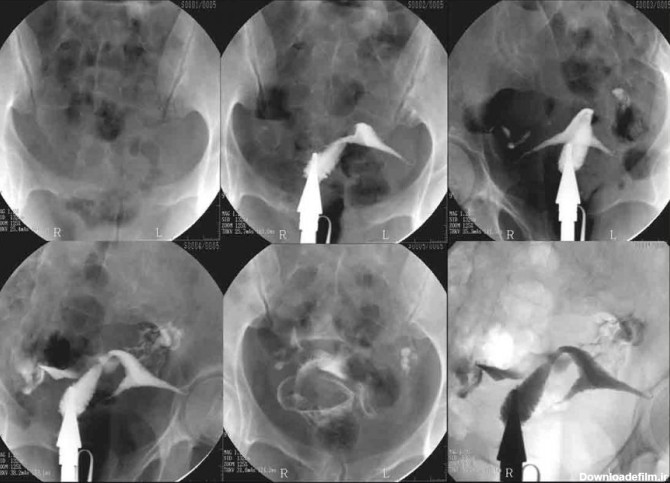

سلام بچها از این عکس رنگی سر در میارید؟ چسبندگی رحم وجود داره؟ بارداری ممکنه یا نه؟

عکس رنگی رحم یا هیستروسالپنگوگرافی یکی از روش های تشخیصی شیوه ی تصویربرداری با اشعه ایکس است که معمولاً برای بررسی آناتومی رحم و لوله ها انجام میشود. عکس رحم